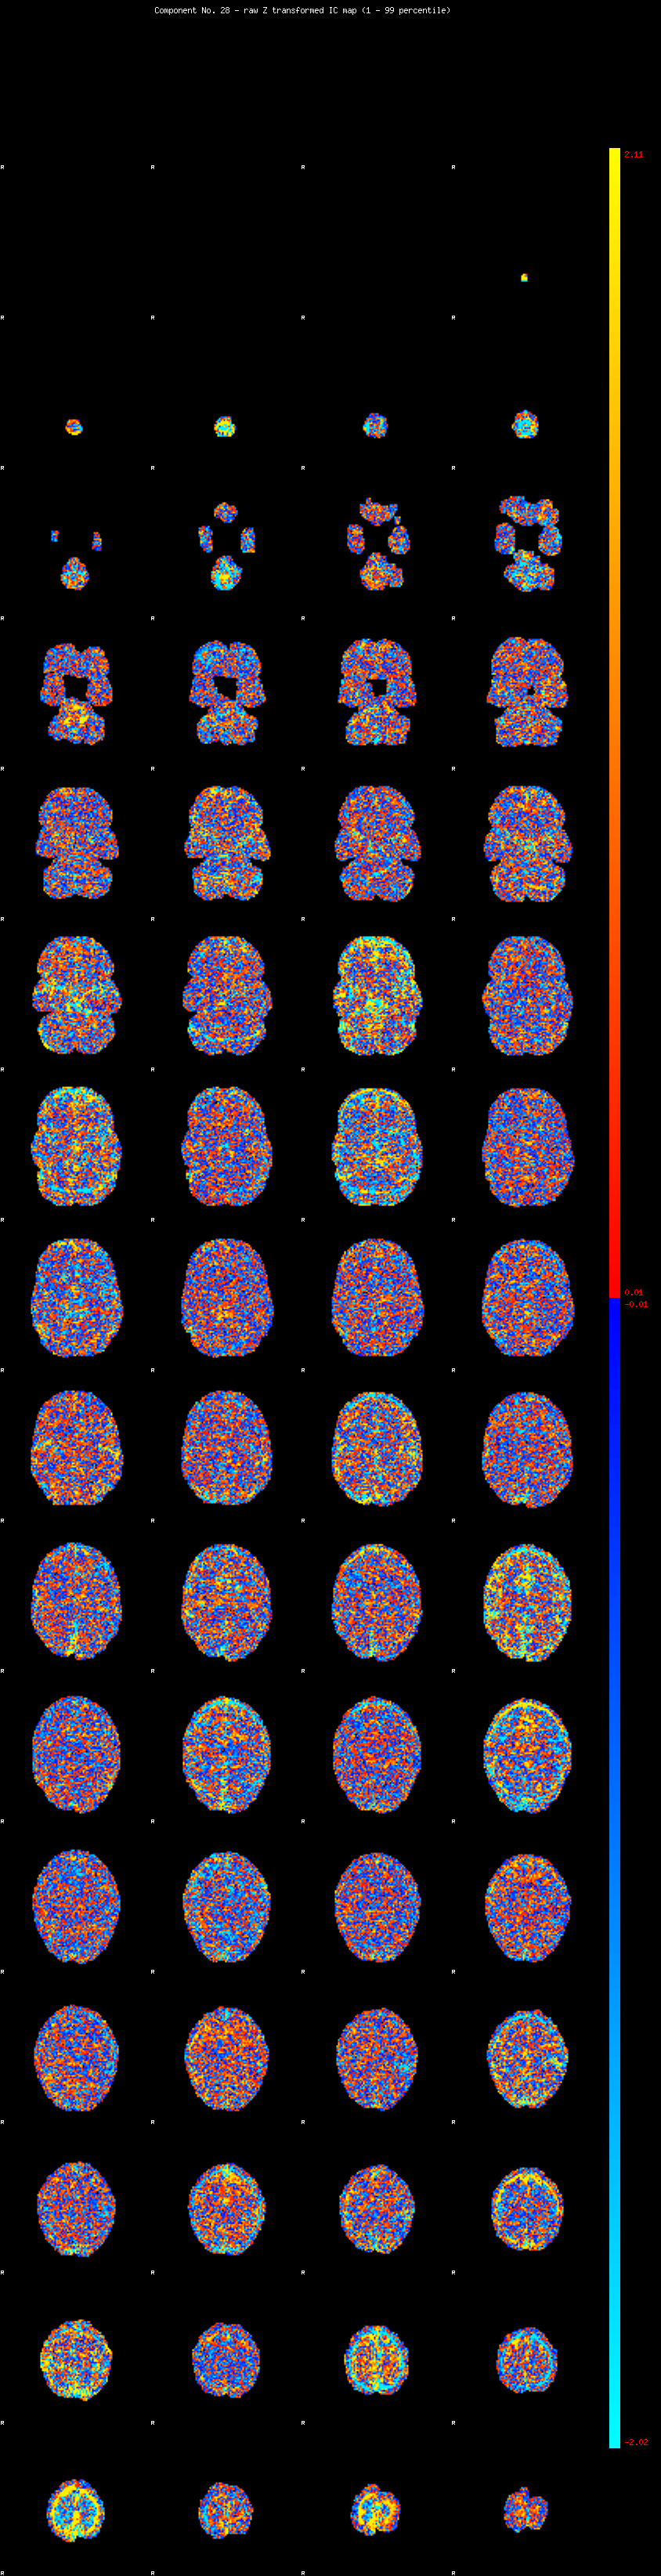

IC_28 Mixture Model fit

Means : -0.000000 2.930921 -2.556320

Vars : 1.000000 3.653941 2.269429

Prop. : 0.925134 0.038218 0.036648